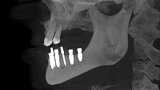

Implantacja z wykorzystaniem szablonu nawigacyjnego 3D